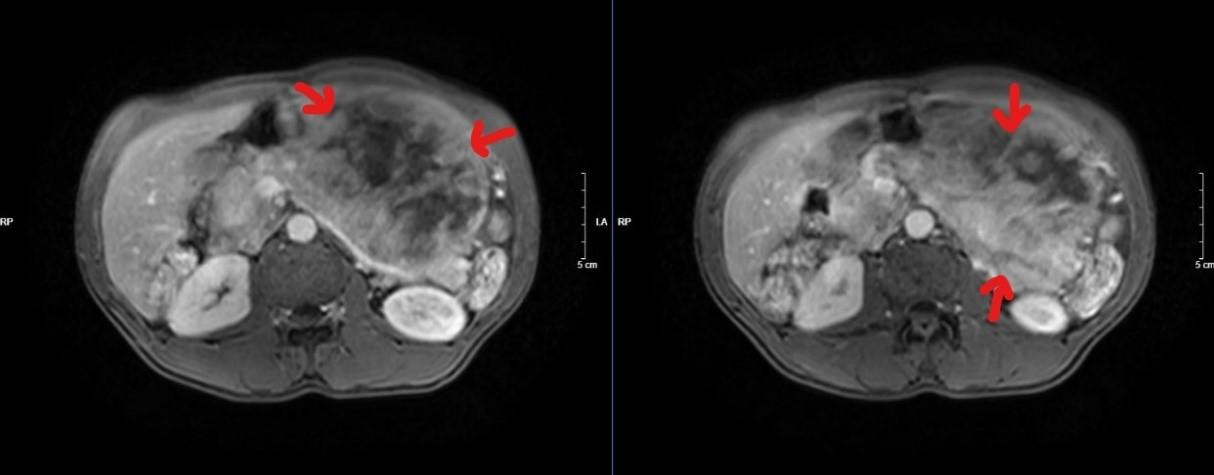

![]() |

| Phim cộng hưởng từ - Hình ảnh khối lớn nửa bụng trái xâm lấn tụy. Ảnh: BS cung cấp |